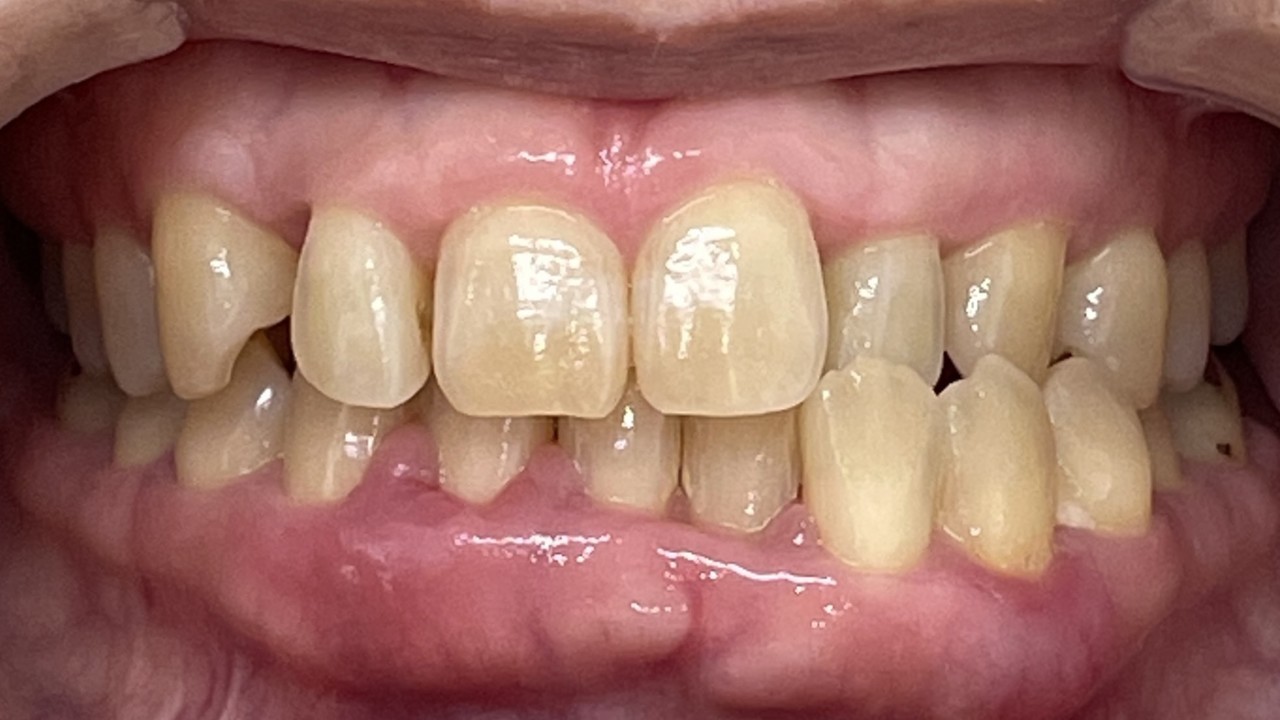

Before

After

矯正の種類 / SmileTRU

年齢・性別 / 10代女性

主訴  /  上顎前歯部が曲がっている(捻転症例)

治療期間 / 8ヶ月

費用 / 模型・3Dデータ診断 35,000円(税別) 上顎のみマウスピース14枚 308,000円(税別)

※マウスピース交換時別途調節料3,000円(税別)

副作用 / 口内炎・歯の移動に伴う痛み・知覚過敏 ※数日で収まる場合が多いです

リスク / 後戻り防止の為、夜のみマウスピースで保定を指示